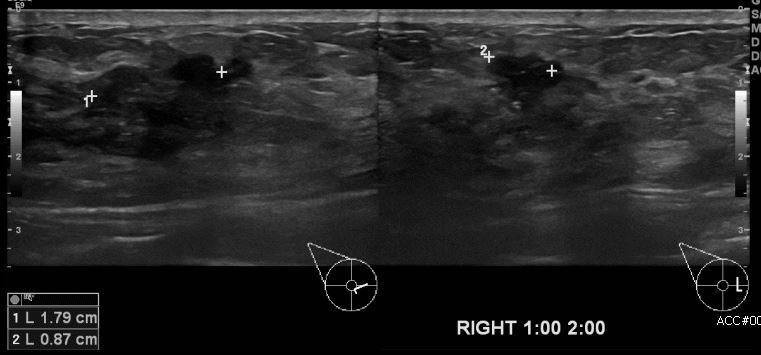

상기환자 우측 만져지는 멍울로 내원하신 40대 여성분으로 본원 초음파상 우측유방 1시에서 2시 방향에 만져지는 멍울 조직검사 시행하여 우측 유관암 진단되었습니다.